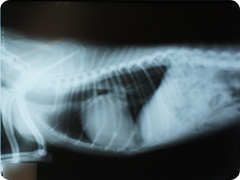

- 胸水

- 心不全や腫瘍などが原因で胸水がたまると、肺が充分膨らまないために十分な酸素が取り入れにくくなります。そのため呼吸回数を増やして補おうとします。

-

胸水

胸腔内にたまっている水はX線写真では白く見えます。この胸水に含まれている細胞を検査して診断していきます。この胸水には腫瘍細胞が認められました。

リンパ腫

腫瘍の形がみえます(胸腺型リンパ腫)。

リンパ腫治療後

化学療法により腫瘍は小さくなります。